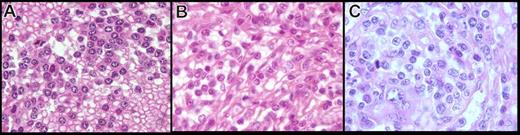

In PB, cytologic features showed a homogeneous infiltrate of small to medium-sized cells with round or oval nuclei, sometimes eccentrically placed, and dense, often clumped chromatin. The cytoplasm was variable in amount and was moderately basophilic with well-visible villous projections, unevenly distributed around the cells and with a polar distribution (Figure 1A-C). In the majority of cases, villi were broad based, whereas in others, they were rather thin. The nucleolus was small or not visible in the large majority of the cells, and was rarely prominent. Some lymphoplasmacytoid cells were often observed. A significant percentage of medium to large cells with a prominent nucleolus was present in only 4 cases, which was consistent with tumoral progression in 2 cases and transformation in the 2 others (Figure 1C). The percentage of blood infiltration by those particular VLs was always high, ranging from 26% to 91% of all lymphocytes (median, 60%).

Peripheral blood smear (May-Grünwald Giemsa staining, original magnification ×100). (A-C) Villous lymphocytes in the present series: long and large and broad-based villi unevenly distributed around the cell, round nucleus with clumped chromtin. (D,E) Cells in classical SMZL with short cytoplasmic projections (VLs). (F) Hair cells in HCL.

In formalin-fixed, paraffin-embedded tissue, the cytology had two distinctive features (Figure 3A,B). First, in 5 cases, the cells were small with round hyperchromatic nuclei, clumped chromatin, and basophilic cytoplasm, giving a plasmacytoid appearance. In 6 other cases, the cells were larger and presented a more irregular nucleus, having less-clumped chromatin with a less basophilic and abundant cytoplasm, except in 1 case, where the cytoplasm was clear and abundant. In 2 cases, we observed a mix of both round and irregular nuclei with more atypical cells, a prominent nucleolus in almost all nuclei, and an increase of large cells and mitoses (Figure 3C). Those cases also were considered transformed on imprints.

Spleen cytology in paraffin-embedded tissue of the present series (hematoxylin-eosin safran stain, original magnification ×100). The cells observed in the present series on spleen sections showed two distinctive features: (A) cells with round nucleus, clumped chromatin, and abundant basophilic cytoplasm, (B) cells with more irregular nucleus, less clumped chromatin, and less abundant cytoplasm, and (C) an increase in atypical cells with a prominent nucleolus, increase in large cells, and mitosis in morphologically transformed cases.